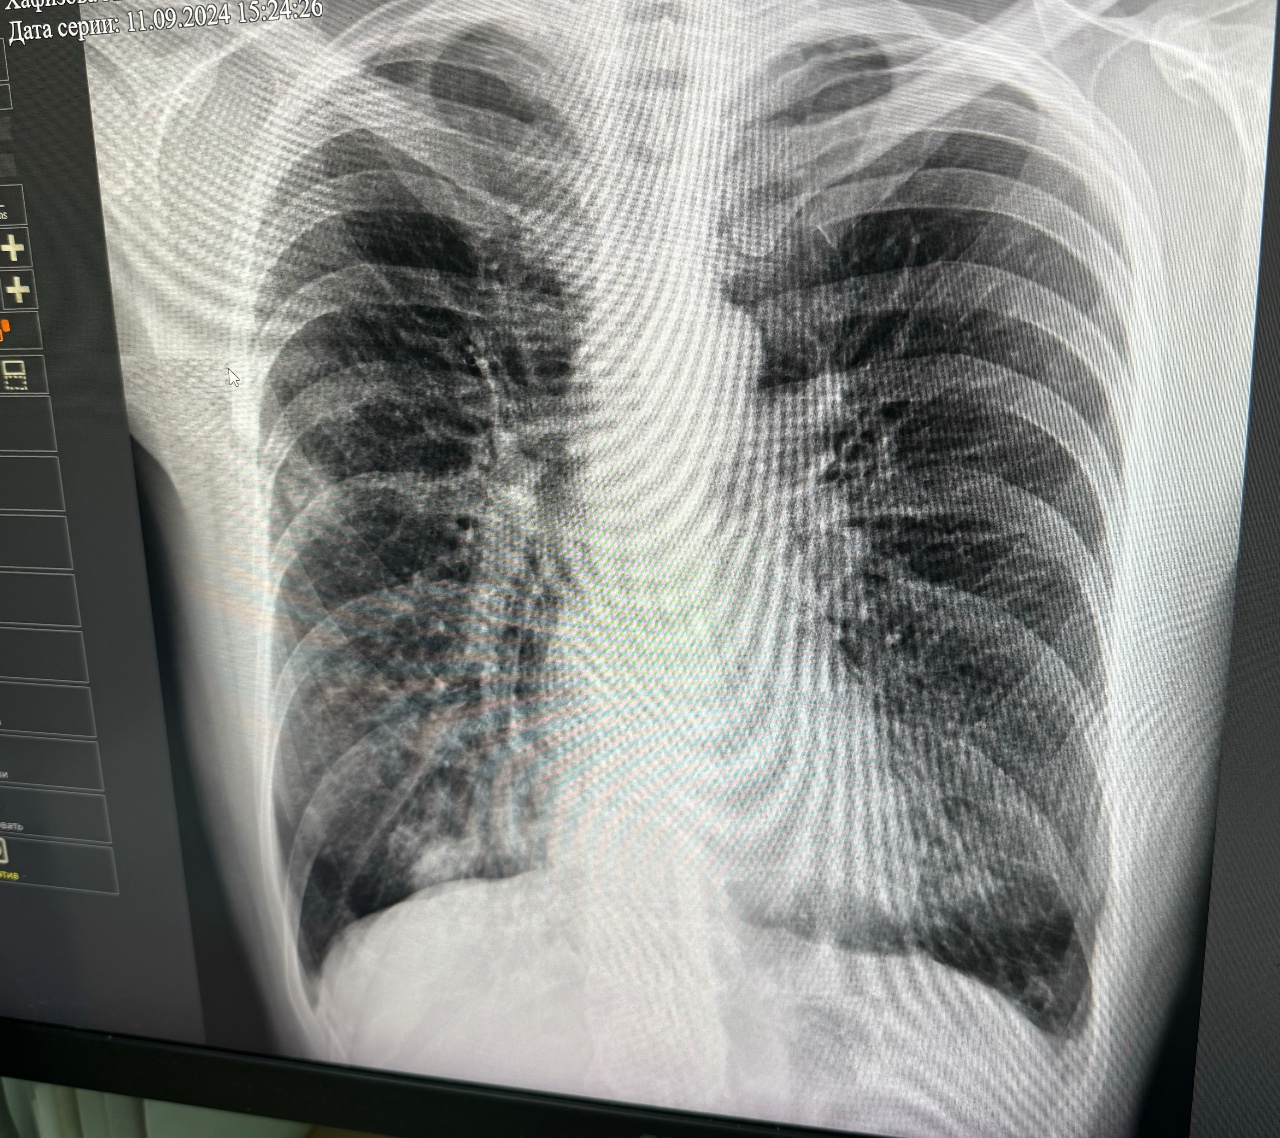

Доброго времени суток! В сентябре 2024 года я переболела пневмонии, температура долго держалась, лежала в больнице 2 недели, повторила рентген снимок в мае 2025 года, посмотрите пожалуйста и дайте свой комментарий, спасибо заранее ????????

Здравствуйте! На представленном снимке признаков пневмонии нет. Отмечаются эмфизематознве изменения верхних отделов, локальный фиброз справа. Надо видеть предыдущие снимки, стоит сделать спирография с пробой на 400 мкг сальбутамола для исключения астмы или ХОБЛ

Динамика положительная пневмония полностью разрешилась Спирография нужна, также необходима вакцинация от пневмококка

Да, совпадает. Постпневмонический фиброз не относится к смертельным заболеваниям и не требует лечения. После любой травмы или большого воспаления остается рубец, это нормально, это законно и это физиологично. Вы же не лечите рубец на руке после пореза через 2 недели после того как рубец затянул рану.

Есть смысл в поддержании противовирусного и антибактериального иммунитета в виде пневмококковой и противогриппозной вакцин. Необходимо пить не менее 1.5 литров воды в день, неплохо работает тонзилгон в плане восстановления слизистой бронхов и легких после воспаления.